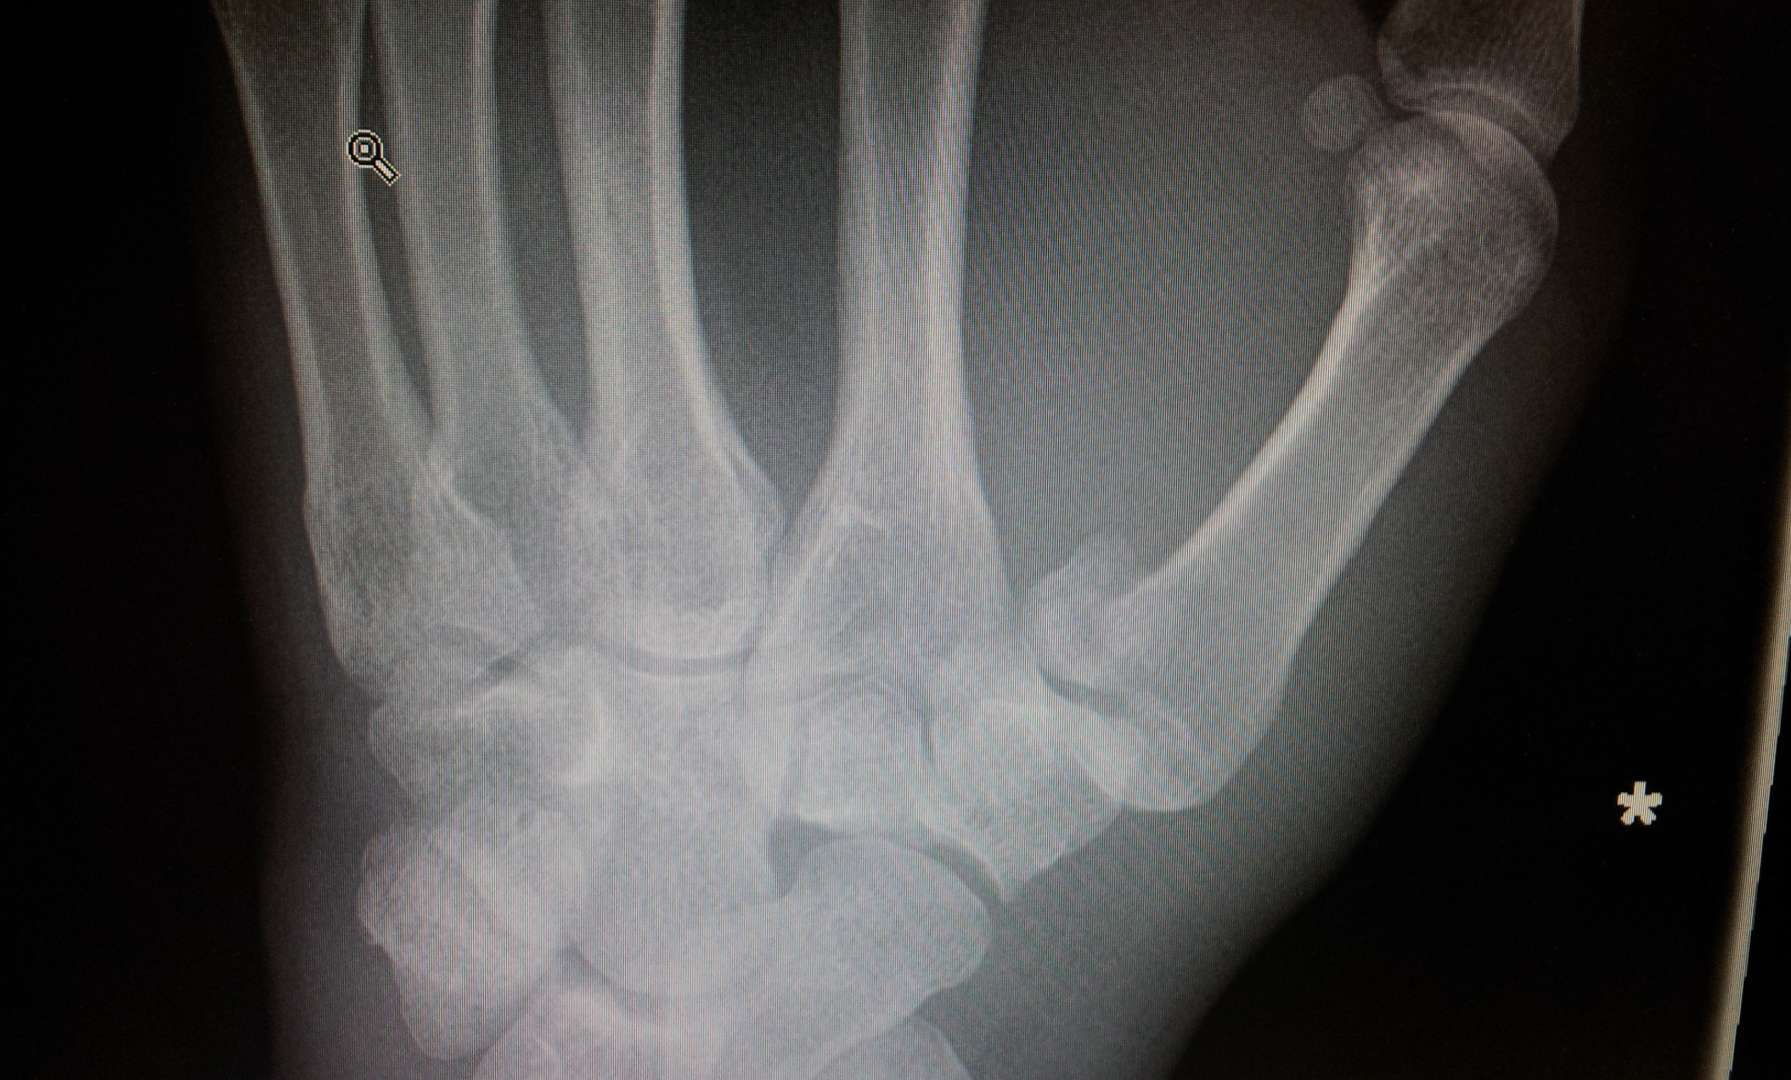

Did mine last night coming off bike hard on some acorns in the woods. Minor injury clinic was great. In Xray plaster cast and out in under an hour. Now awaiting hand-clinic appointment to see if it needs pinning (likely by all accounts).

Like you say, treatment usually involves some kind of fixation. Typically a K-wire approach that keeps things in place while healing.

Did mine in mid-September 2014. Bennetts fracture. Broke it on the Saturday*, surgery on the Tuesday. Two pins to keep my thumb in place. Around 6 weeks in plaster. Non-dominant hand so still managed to wipe my own arse. Back at work a couple of days later. Looking back at Strava, my first ride back was commuting after 8 weeks and I remember that being sore, no proper MTB ride until the festive break (approx 12 weeks post injury). Hand remained swollen for ages afterwards and I still have a (very) small bit of restricted movement now - natural resting position for of thumb is it sticks out a bit more than before. Feels tighter even now if I stretch my thumb tip over to touch my pinkie, for example.

Cheers for all the support. Hopefully going in to get it wired together next Friday (I will believe it when I see it). Then 4 weeks till pins come ou t and another 2 weeks in plaster after that. Buggeration